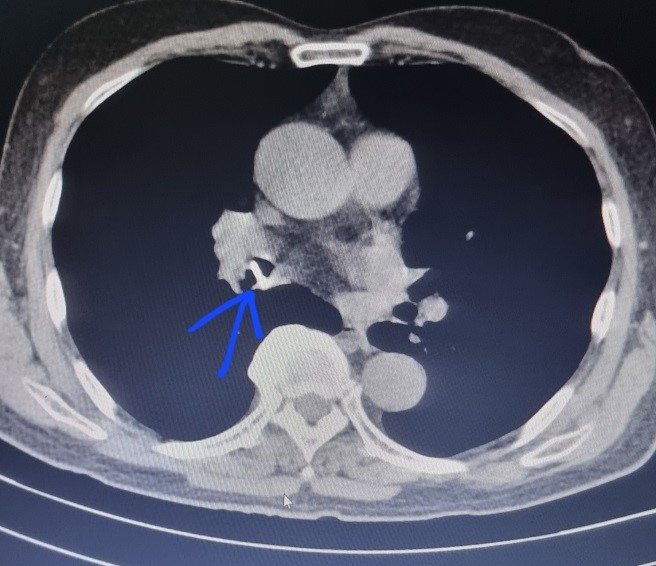

Bệnh nhân nam, 76 tuổi, có tiền sử đặt Stent mạch vành và đang dùng thuốc chống đông từ năm 2021. Khoảng 2 tuần gần đây, bệnh nhân có biểu hiện ho, khạc đờm, đau ngực, không rõ tiền sử sặc hay biểu hiện của Hội chứng xâm nhập. Bệnh nhân nhập viện và chụp CT ngực phát hiện dị vật phế quản trung gian phổi Phải.

Hình 1: Hình ảnh dị vật trên Cắt lớp vi tính